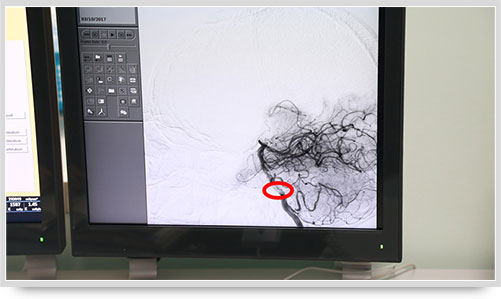

45岁的朱姓患者因“多发性腔性脑梗塞”头晕不明,接受了全脑血管造影术,术中显示他的颅内椎动脉血管痉挛(红圈内为病变部位)。据李主任介绍,以前像脑梗塞等脑血管疾病只能被定位到脑的功能区域,无法确定责任血管,而实施全脑血管造影术就能精准地找出病变血管,好比揪出了造成脑梗塞的“祸首”,大大提高了脑血管疾病的诊治水平。